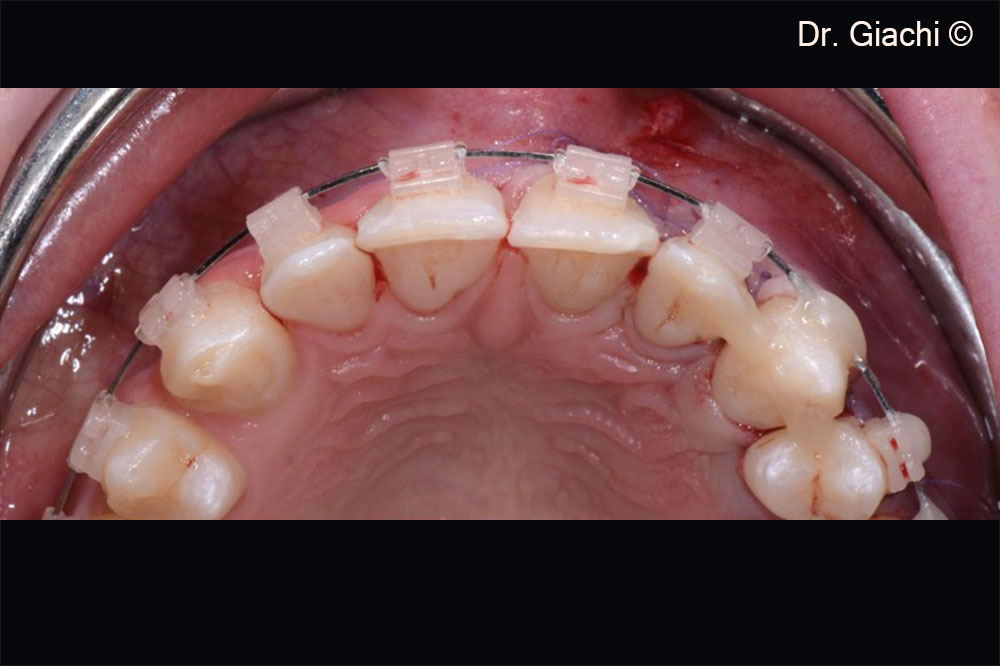

Một bệnh nhân nam (16 tuổi) có răng nanh trên không thể phục hồi bằng phương pháp chỉnh nha truyền thống.